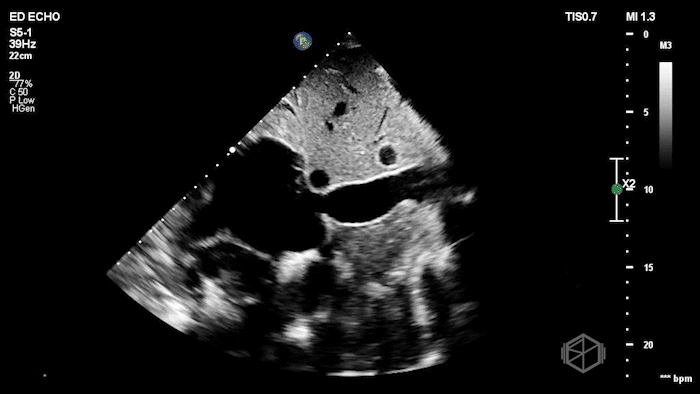

Their Cardiac POCUS showed:

POCUS showed marked left ventricular wall thickening, a dilated right ventricle, biatrial enlargement, a small LV cavity, and a small pericardial effusion. The left ventricular myocardium also had a mildly granular or β€œspeckled” appearance.

Diagnosis: Findings concerning for infiltrative cardiomyopathy (cardiac amyloidosis)